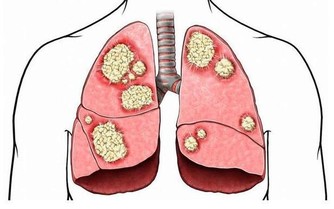

小欣在家人陪同下去到醫院檢查,醫生剛看到小欣的第一眼,就判斷,小欣的肝不行了。

一同檢查下來之後, 小欣果然是肝癌晚期,手術已經無法實行,只能等著生命的結束。

近年來因濫用減肥藥而導致肝臟損傷的病人不在少數,因為不少減肥藥都含有乾擾脂肪代謝的成分。